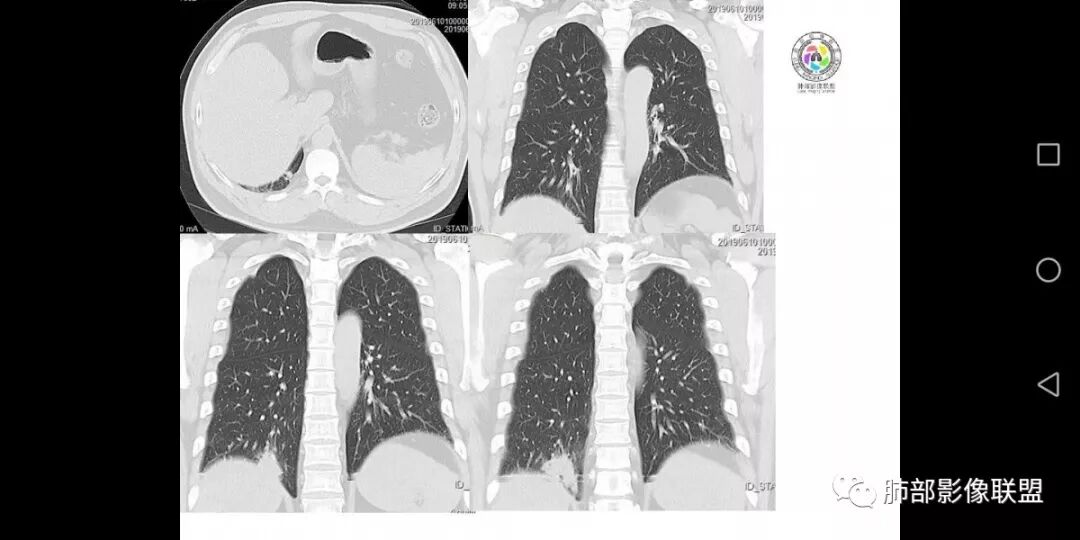

患者男,45岁,因乏力、低热、心悸入院,最高体温38℃,偶有咳嗽、无咳痰、咯血,肿瘤标志物阴性。

影像资料

右肺下叶结节,边界清,周围有胸膜牵拉,内部见坏死,低热,考虑结核。

右肺下叶后基底段结节边缘收缩平直 ,局部膨隆  ,延迟强化,内见坏死,考虑炎性肉芽肿。

右肺下叶后基底段胸膜下肿块,边缘平直、凹陷为主, 局部膨隆 ,周围模糊毛玻璃影及锁条, 内见坏死,明显强化,较均匀,下缘糊墙,考虑炎性,慢性脓肿?鉴别炎性合并肿瘤。

中年男性,乏力  低热入院,胸CT:右肺下叶后基底段结节样病变,病灶周围可见细支气管扩张,病灶边缘可见短软毛刺,病灶周围有毛玻璃影,冠状位肺窗病灶与膈胸膜呈宽基地,纵隔窗可见病灶内空洞及低密度区,增强明显强化及延迟强化,考虑良性感染性病变,隐球菌肺炎?,结核?。但在冠状位肺窗有一支细支气管在病灶旁有截断,还得除外肺癌的可能性。

中年男性,低热,咳嗽,偶有咳痰,右肺下叶可见一不规则结节影,边缘有收缩,有膨隆,周边可见磨玻璃影,可见分叶,延迟强化,内有坏死,似有颗粒感,空泡,胸膜有牵拉,倾向于腺癌,鉴别炎性病变。

患者主要表现低热,乏力,伴少量咳嗽等症状,右肺后基底段不规则肿块影,有"平直,刀切征",局部有膨隆,周围模糊,有晕征,分叶,有细软毛刺,部分胸膜牵拉,中间有低密度坏死,有空泡,延迟强化,良性征象稍偏多点,考虑隐球菌?需排除周围性腺癌,淋巴瘤。

男,45岁;乏力、低热、心悸,38°,偶咳;症状像结核,但无钙化,无积液;三期:35-57-71偏心空洞,冠状位胸膜有牵拉力:需考虑鳞癌,男性,45岁,年龄偏小,吸烟史?

不均匀强化,三期强化形式是否符合鳞癌,渐进性强化?结核:空洞,渐进性强化,段样分布,但没有卫星灶;

处置:结核相关检查,仔细观察与支气管关系,按我的习惯,多b值观察细胞密集程度。

中年男性,右下肺叶后基底段结节影,周围有晕,边缘软毛刺,收缩力弱,边缘平直凹陷,支气管进去后截断,长轴与胸膜平行,中心有坏死,延迟强化,考虑炎性病变,隐球。

中年男性,乏力,低热,右肺下叶后基底段近膈肌缘小团块样病灶,边缘平直,部分内凹,周围磨玻璃,边缘模糊不清,周围少许毛刺,柔软,增强后明显渐进性强化,其内可见少许低密度区,边界清晰,考虑感染性病变,op合并坏死可能。

右下叶病灶,周围ggo边界清,轴位病灶似乎有收缩,平直征,但是冠状重建可以看看病灶边缘膨隆,强化不均匀,持续强化,结合病史首先考虑肺癌,腺癌可能性大,鉴别隐球,op。

患者中年男性,以乏力、低热、心悸入院。胸部CT:右肺下叶后基底段近胸膜实性结节灶,病灶周围磨玻璃模糊影,可见短毛刺,边缘呈刀切、平直,冠状位肺窗病灶与膈胸膜呈宽基地,纵隔窗可见病灶内空洞及低密度区,增强明显强化及延迟强化,综合考虑良性感染性病变。肺隐球菌病可能大,机化性肺炎、腺癌次之,结核待排。

中年男性,低热乏力入院,右肺下叶后基底段结节影,边缘收缩平直,周围有晕,有细软毛刺,内有低密度坏死,明显强化。有胸膜牵拉,考虑感染性病变:op?隐球菌肺炎?肺结核?鉴别肺癌!

中年男性,以低热、乏力为主要症状,右下叶近胸膜病灶,支气管进入但有近端堵塞,周围有短毛刺,磨玻璃影边界不清,周边有条索状纤维灶,病灶有强化和点状坏死,考虑炎性肉芽肿可能性大,隐球?目前整体考虑炎性,但具体是啥是猜的。

右肺下叶后基底段结节,边缘较清,有浅分叶,病灶长轴与胸膜平形,以平直收缩为主,局部稍膨隆,有长短不一的毛刺,边缘模糊,周围有小片状模糊hggo,中心有小空泡或小空 洞,内壁光整,增强后延迟强化,提示会不会有纤维组织成份,而且空腔内壁强化明显且完整,邻近胸膜有糊墙,考虑炎性病变,机化性肺炎合并脓肿?鉴别癌。